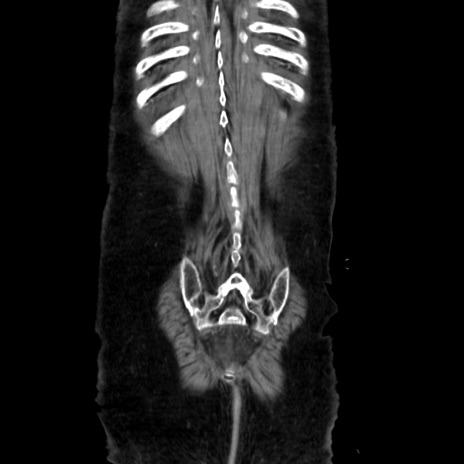

症例40(冠状断像)

【症例】90歳代女性

【主訴】腹痛・嘔吐

【現病歴】 食欲低下、嘔吐があり昨日他院受診。肺炎と診断され入院となる。入院後より腹部全体に圧痛あり。胃管留置され経過みていたが、症状持続するため、

当院転院となる。

【既往歴】胸椎圧迫骨折、胆石症

【身体所見】腹部:中央に激痛あり、圧痛あり、反跳痛不明

【データ】WBC 17100、CRP 18.82

矢状断像